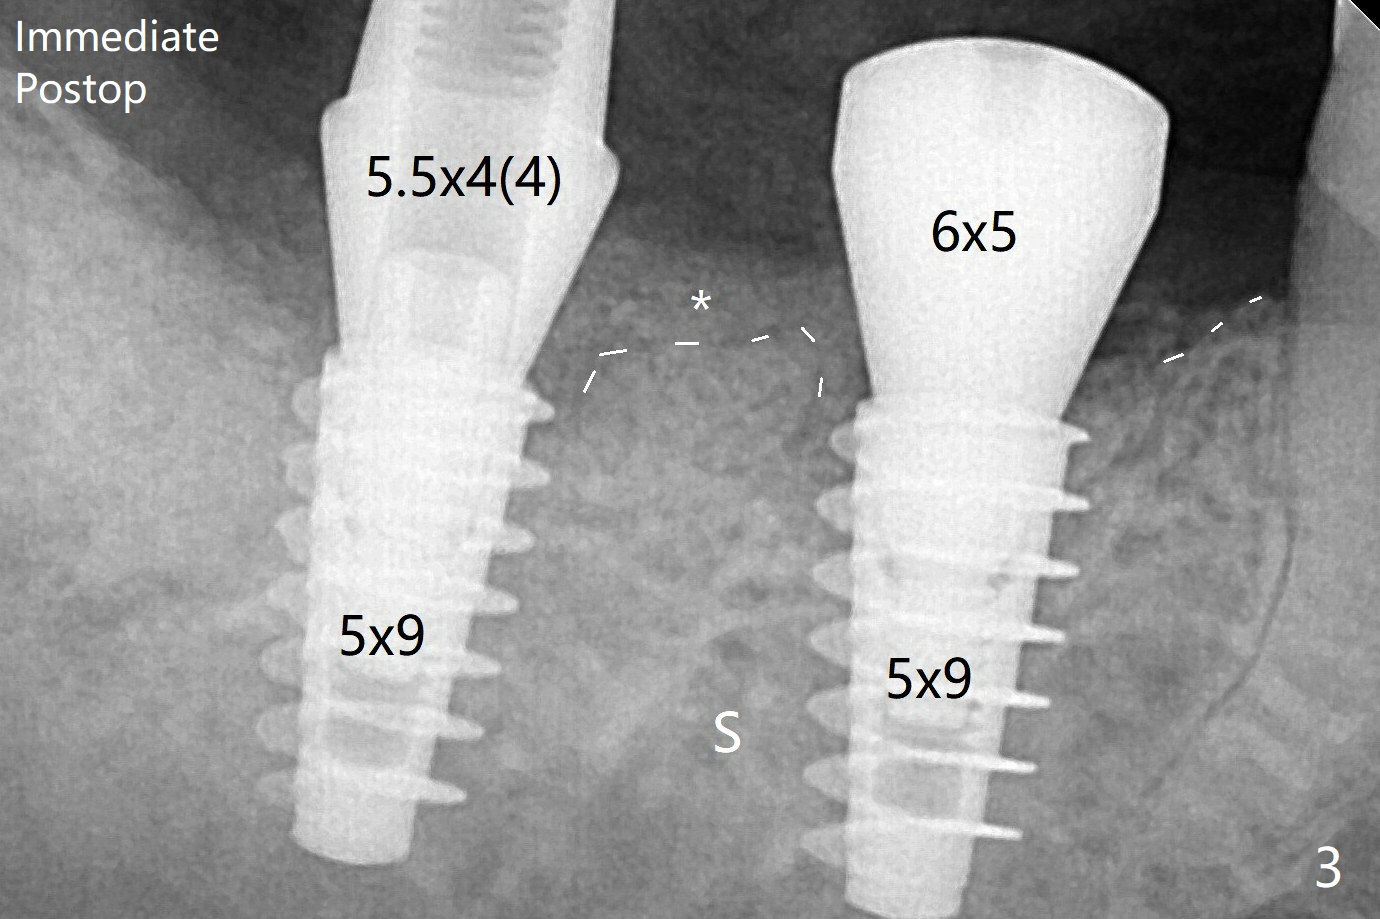

植入植体,6扭力低(因为植入近中窝),7高(6,7之间牙槽骨),所以安置愈合(6x5毫米)和修复(5.5x4(4)毫米)基台。原来导板设计把植体植入牙槽嵴(图三:白虚线)下1-2毫米,自动提高植体间牙槽嵴,接着把钻洞产生的骨粉放在后者上缘(*),由近中和远中基台固定。术后3个月7牙槽窝愈合(位点保存后10个月,图五:*),植体间牙槽嵴仍旧高(箭头),6放置修复基台,准备做临时牙冠。